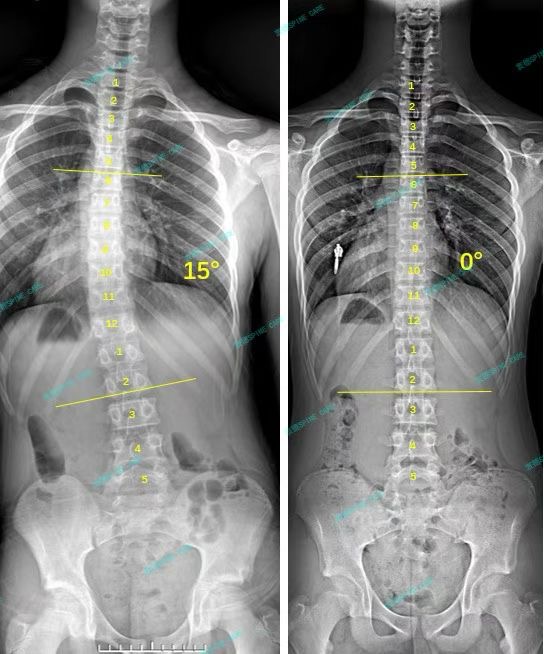

衷德脊柱,我们只关注侧弯保守治疗~

Zhongde Spine, bending no breaking ~